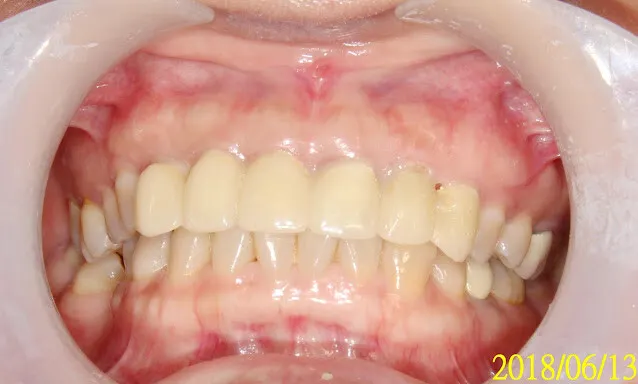

請注意開始是2017,花了一年多,才終於走到裝正式假牙

再經過一年,假牙看起來更自然了,當初剛裝假牙時的牙齦,病人自己說大概一個多月就自動長好恢復了